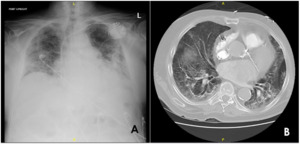

A 75-year-old male with chronic obstructive pulmonary disease (COPD) and congestive heart failure (CHF) presented to our emergency department with a chief complaint of acute worsening shortness of breath. As part of the dyspnea workup, computed tomography was obtained of the chest, which demonstrated diffuse interstitial lung thickening from edema with scattered emphysematous cysts [Figure 1]. He was subsequently admitted to our hospital for acute hypoxic respiratory failure and initiated on diuretics and antibiotics for suspected COPD and CHF exacerbation. Continuous positive airway pressure was started with albuterol/ipratropium nebulization every four hours.

It was noticed that afternoon he had developed abdominal distension and scrotal swelling, for which an immediate screening chest x-ray was performed, showing pneumoperitoneum. This resulted in surgical consultation due to concern for bowel perforation and a stat CT of the abdomen and pelvis with contrast to be obtained [Figure 2]. The CT imaging demonstrated that the appearance of pneumoperitoneum was related to pneumomediastinum and subcutaneous emphysema that extended circumferentially around the abdomen and anteriorly down to the scrotum in the setting of CPAP.